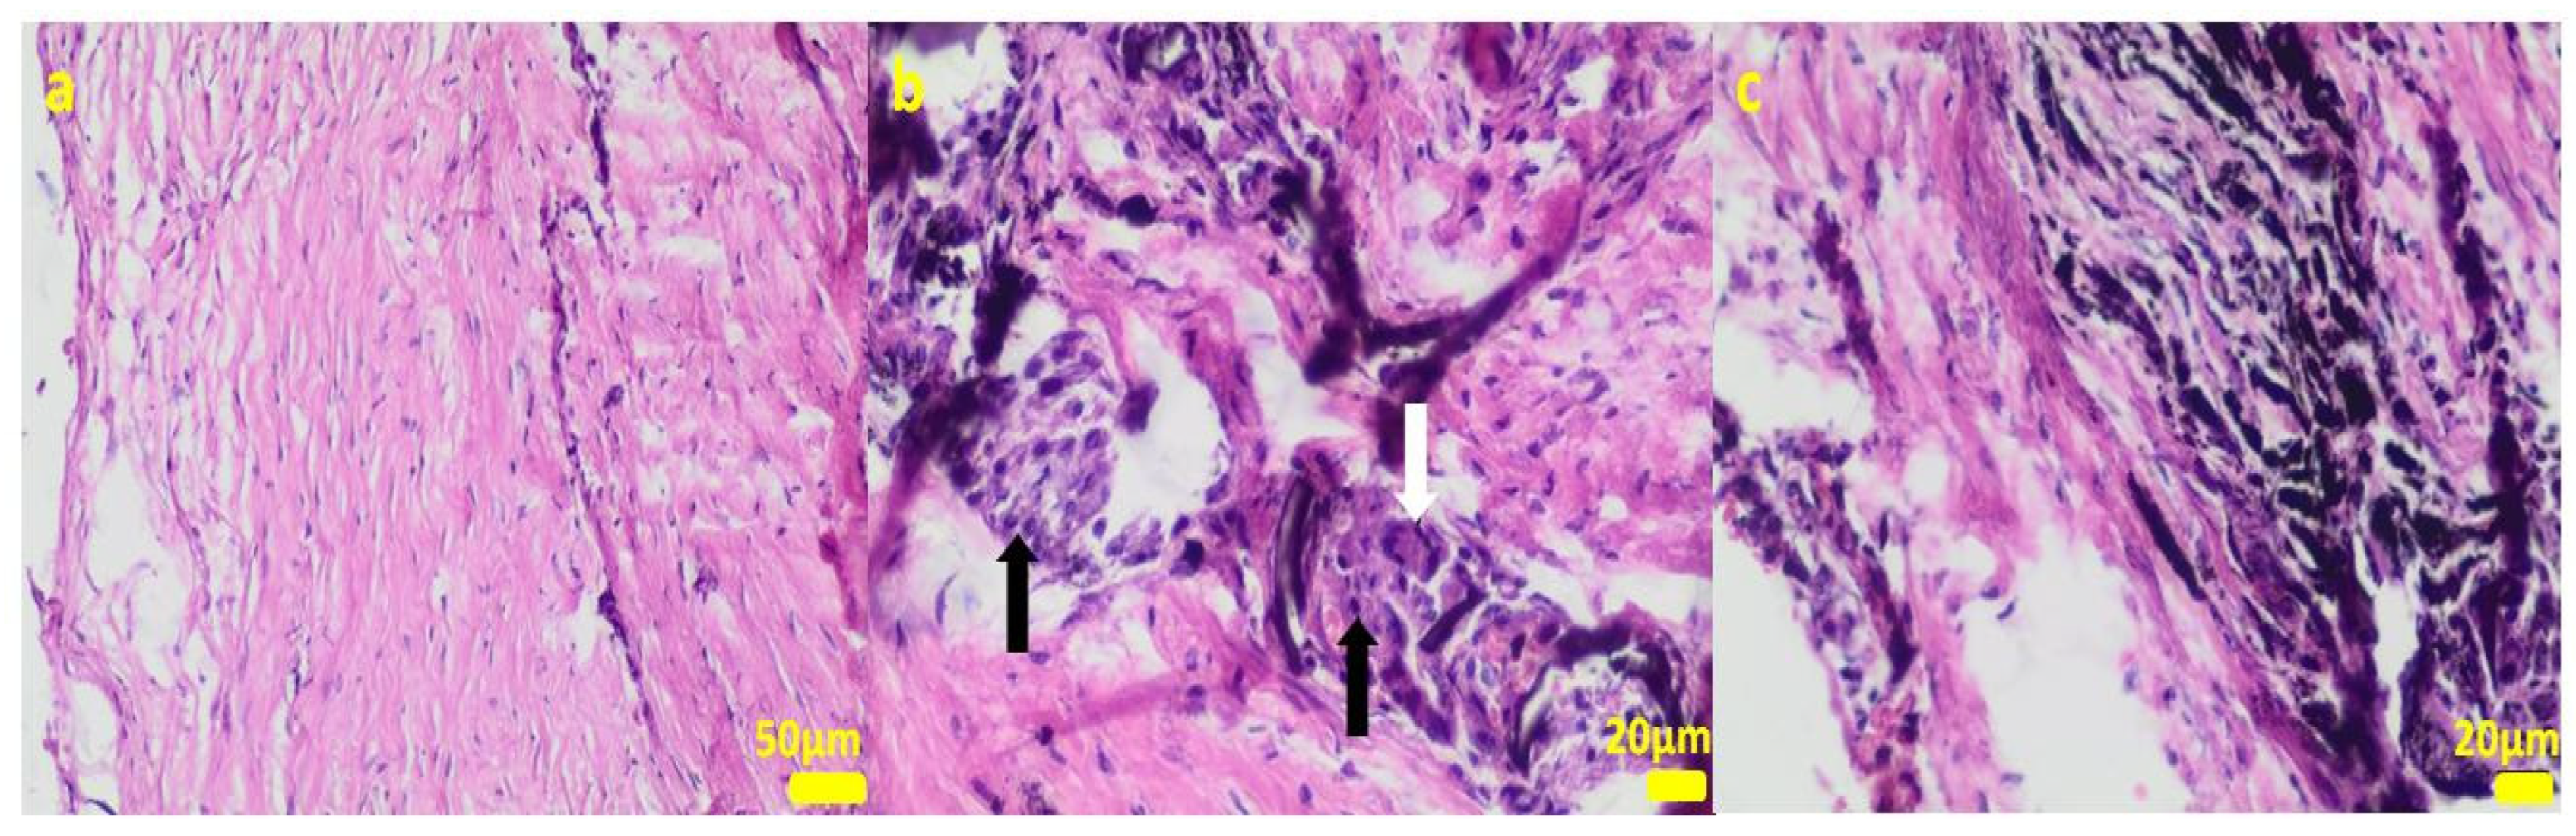

2.1. In Vitro Examinations

2.2. In Vivo Study

4.3. Cell Cultures